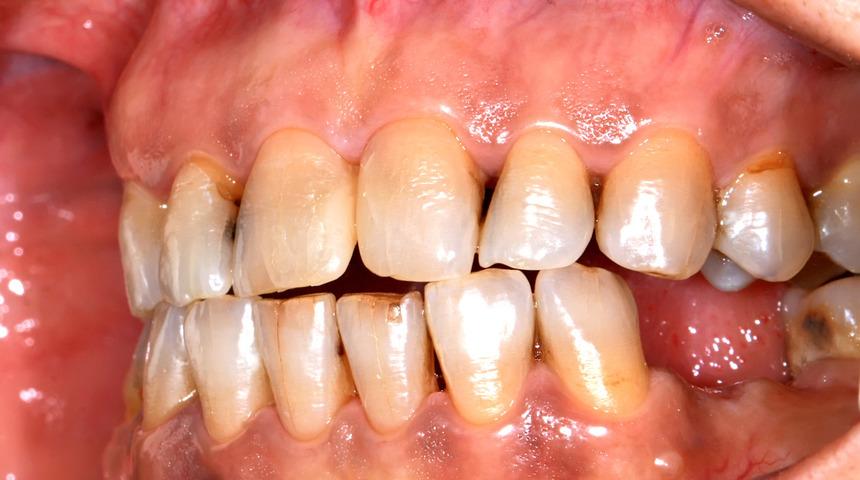

Baş-boyun kanserleri nedeniyle radyoterapi gören hastalarda oluşan ağız-diş sağlığı sorunları ciddi sıkıntılara neden olabiliyor. Ancak alınacak tedbir ve koruyucu uygulamalar bu komplikasyonların önlenmesini sağlıyor. Ağız, Diş ve Çene Cerrahisi Uzmanı Dr. Nihat Tanfer, radyoterapi uygulaması öncesinde hastaların mutlaka diş hekimine başvurmaları gerektiğini söylüyor. Radyasyona bağlı ağız mukozasındaki hücre ölümleri, genellikle tedaviden 5-10 gün sonra başlayıp 3-4 hafta sonra tamamen iyileşen ve mukozit adı verilen küçük ağız yaralarının oluşmasına neden oluyor.

Ağız, Diş ve Çene Cerrahisi Uzmanı Dr. Nihat Tanfer, radyoterapinin ağızda görülen etkilerini şu şekilde özetliyor: Işın, tükürük kalitesini bozuyor, tükürük akışının bozulmasına bağlı olarak;

Ağız kuruluğu başlıyor ve takiben kanama meydana geliyor.

Tükürüğün çürüğü önleme etkisi azalıyor.

Ağzı ve dişleri temizleme fonksiyonunda azalma oluyor.

Tat alma duyusu bozuluyor.

Dişlerde soğuk-sıcak hassasiyeti oluyor.

Yutma, çiğneme ve konuşma fonksiyonlarında zorlanma meydana geliyor.

Osteoradyonekroz, yani radyasyona maruz kalmış kemikte hücre azalmasına bağlı oksijen yetersizliği nedeniyle gerekli iyileşmenin olmaması sonucu kemik dokusu canlılığını kaybediyor.

Radyoterapiden sonra tedavi sahasındaki damarlarda kan akımını azaltan bir daralma ve tıkanma söz konusu oluyor. Yutma, çiğneme ve konuşma fonksiyonlarında çok ciddi zorlanmalara neden oluyor.

Radyasyon sahasında dişeti bağlarındaki zayıflamadan dolayı olan sallanma nedeniyle sıklıkla diş kayıplarına rastlanıyor.